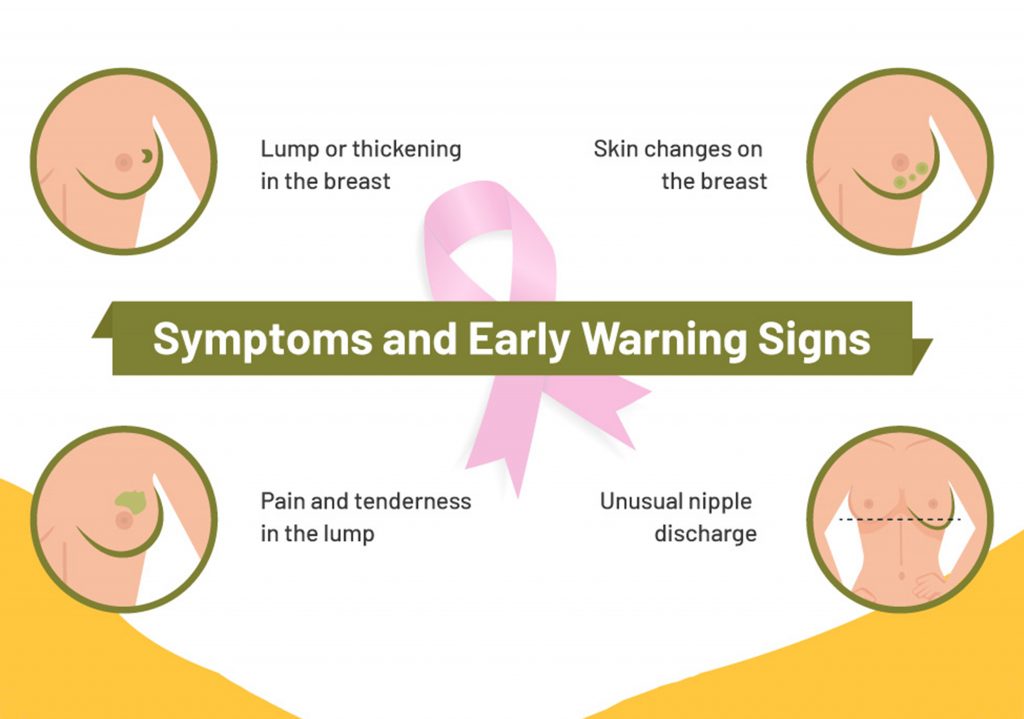

အများစုက ရောဂါဖြစ်စမှာ သိသိသာသာ လက္ခဏာမပြပဲ ရင်သားတစ်သျှူး တစ်ချို့ ထူလာပြီး အလုံးအကျိတ်ဖြစ်လာတဲ့အချိန်မှ စပြီးသတိပြုမိကြတာပါ။ ရင်သားမှာအလုံးအကျိတ် စမ်းမိတိုင်း ရင်သားကင်ဆာ မဟုတ်ပါဘူး။

♦ ရင်သား နဲ့ ချိုင်းကြားမှာ အလုံးအကျိတ် ပေါ်လာခြင်း။

♦ ရင်သား အရွယ်အစားနဲ့ ပုံစံ ပြောင်းလဲလာခြင်း။

♦ ရင်သားတစ်ဝိုက်အရေပြားမှာ လိမ္မော်သီးခွံလို အချိုင့်လေးတွေ ဖြစ်လာခြင်း။

♦ နို့သီးခေါင်းပုံစံ နဲ့ နို့သီးခေါင်းတစ်ဝိုက်အရေပြား ပြောင်းလဲလာခြင်း။

♦ နို့သီးခေါင်းမှ သွေးအရည်ကြည်များ ထွက်ခြင်း။

♦ နို့သီးခေါင်း အတွင်းသို့ ချိုင့်ဝင်သွားခြင်း စတဲ့ လက္ခဏာတွေက ရင်သားကင်ဆာမှာတွေ့ရတတ်ပါတယ်။